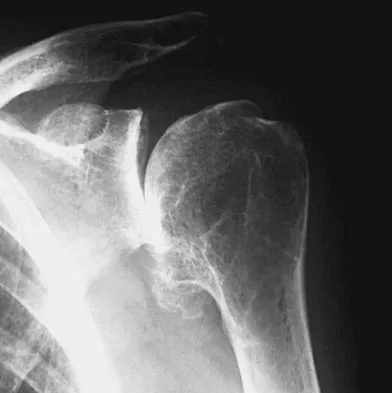

The condition shown in Figures 9a and 9b is most likely the result of

Explanation

The clinical photograph and radiograph show gout, which is the result of urate deposition in the joint and soft tissues. Radiographs frequently reveal periarticular erosions. The crystals are intracellular and negatively birefringent under the polarized microscope. Treatment for acute flares include colchicines, indomethacin, and corticosteroids (including injections). Medications such as allopurinol help prevent recurrent flares. Tophi such as that seen in this patient are often confused with and associated with infection. Wortmann RL, Kelley WM: Crystal-induced inflammation: Gout and hyperuricemia, in Harris ED, Budd RC, Firestein GS, et al (eds): Kelley's Textbook of Rheumatology, ed 7. New York, NY, Elsevier Science, 2005, pp 1402-1429. Trumble TE (ed): Hand Surgery Update 3: Hand, Elbow, & Shoulder. Rosemont, IL, American Society for Surgery of the Hand, 2003, pp 433-457.